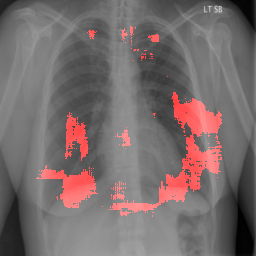

4.2.2 Pulmonary Edema Localization

In order to test the effectiveness of the localization procedure in areas other than the heart region, we chose pulmonary edema which occurs in the lung region. Also, pulmonary edema is detected by the net like white structure in the lung area. No anatomical shape change is associated with the abnormality. We have found that the localization is obtained best when the ROIs of lungs are taken to compute the map. Following the scheme in section 3.4, localization experiment on pulmonary edema is performed as shown in Fig. 8. It has been observed that the classifier is not sensitive to the fine features like septal or Kerley B lines. The localization is mainly obtained in the lung region where excess fluid is observed. Some localization regions are outside the lung region which occurs primarily for the fact that, even though the occlusion center is outside the lung, it occludes lung region and thus the probability drop occurs.

In a similar fashion, additional localization results for Pulmonary Edema is shown in Fig. 13. In Fig. 13(a) and (b) localization of two examples of CXRs with Pulmonary Edema is shown. As stated earlier the classifier localizes in the lung region. This is not the case when normal images are used to localize Pulmonary Edema as seen in Fig. 13(c) and (d). The localizations are obtained in random dense locations such as the sternum or heart. Like the cardiomegaly case, the histogram averages for CXRs with pulmonary Edema (Fig. 13(e)) shows a sensitivity toward pulmonary edema detection while the normal CXRs shows a spread out detection. It is interesting to note that, in the histogram of normal images high probability (¿0.85) is non-existent, thus ensuring low false positive rate. In the test set none of the normal images have been diagnosed as Pulmonary Edema. The failure cases are shown in Fig. 12. These CXRs are with Pulmonary Edema. However, the localization algorithm shows that one of them localizes in lungs whereas the other one shows a localization pattern similar to that obtained in normal CXRs.